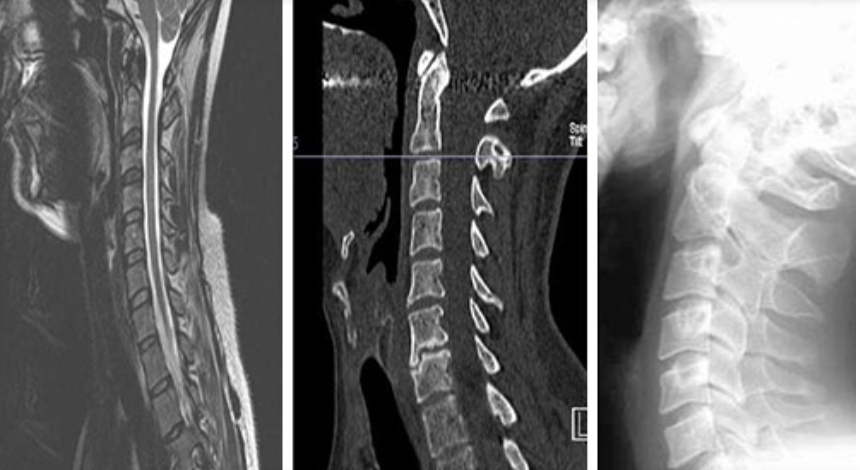

d) CT-Scanning (CT Scan)

It is a computer-assisted special type of X-ray which is more sensitive than ordinary X-rays. It is advised by a consultant where indicated.

e) Magnetic Resonance Imaging (MRI)

It is another form of computer-assisted special type of scanning without using X-rays. It is safe and more sensitive. It is advised by a consultant where indicated.